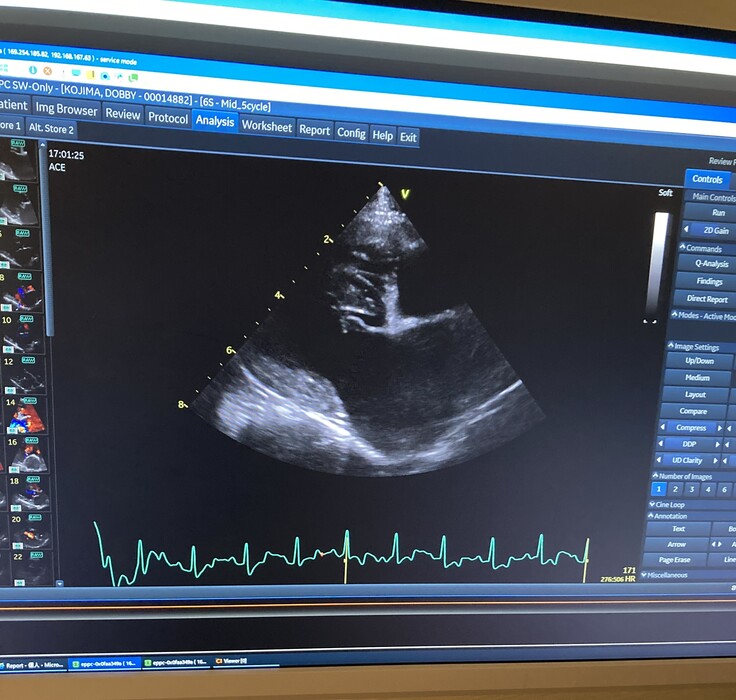

▼心臓のエコー画像

父親や兄と同じ病を患うドビーが、今現在では ステージC に入ってしまっており、酷くショックなことに

今回検査を受けた手術先の病院で、「8ヶ月をめどに見ておいてください。」と余命宣告をされました。

ドビーの場合は、僧帽弁が数カ所”切れてしまっている状態”らしく、

今は心臓が、めいっぱいの状況で頑張ってくれているそうなのです。